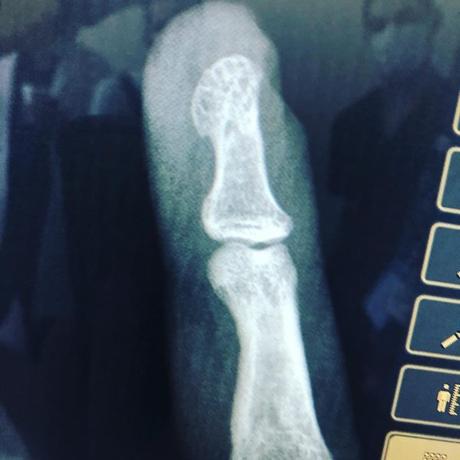

Herida cortante con sierra eléctrica / fractura expuesta de falange / colgajos de avance e injerto cutánea